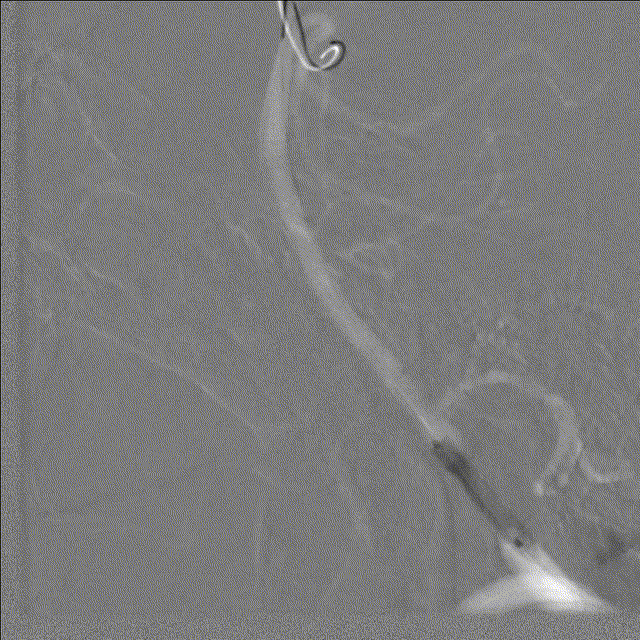

常规消毒、铺巾后,采用改良Seldinger技术穿刺右桡动脉。造影导丝和Sim2造影导管将7F EasyRadial™输送导管置于椎动脉。

正侧位造影提示右侧椎动脉重度狭窄。

200cm微导丝携带微导管路图下穿过狭窄段至左侧大脑后动脉P2段。

沿微导丝送入3.0*15mm 颅内球囊扩张导管至狭窄段给予球囊扩张术。

造影证实狭窄较前明显改善。

撤出颅内球囊扩张导管。

沿微导丝送入3.0*12mm 颅内药物洗脱支架至狭窄段。

准确定位后给予球囊扩张、释放支架。

术后造影造影证实支架打开良好,贴壁良好,无残余狭窄,远端未见明显栓塞表现。